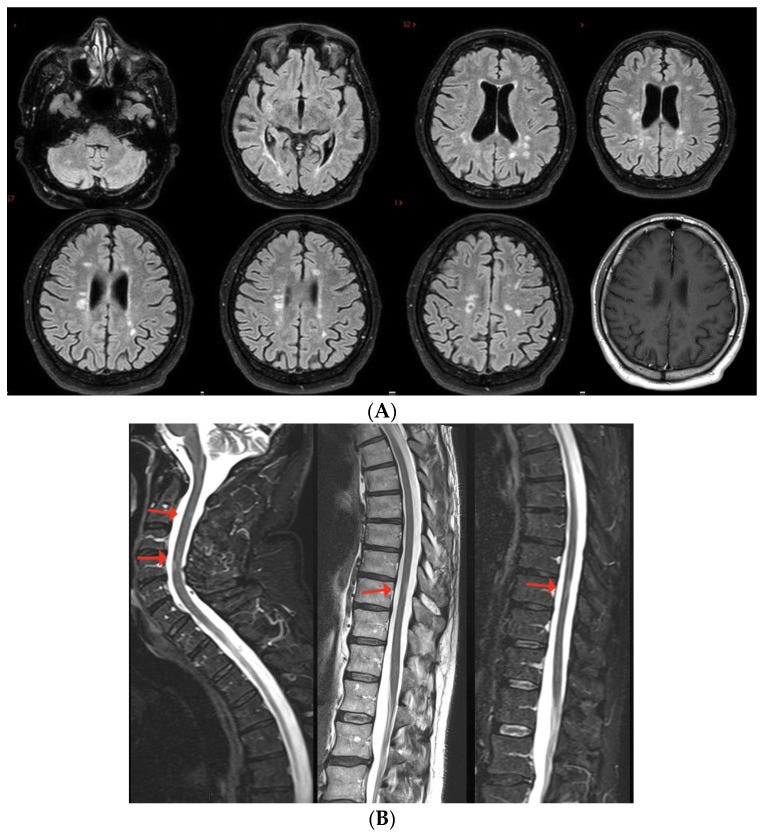

(A,B) Multiple non-enhancing lesions in both brain and spinal cord.